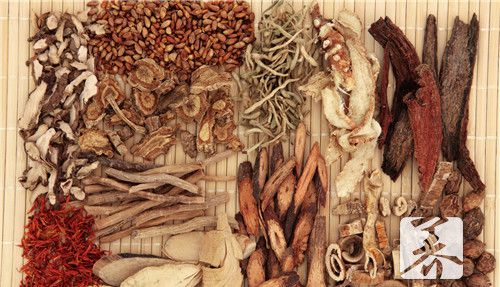

首先,当遇到肾气亏虚的情况时,我们可以考虑使用补肾壮阳的中药。其中,最有代表性的就是“温补类”中药,如杞菊地黄丸、金匮肾气丸等。这些中药主要通过补肾益气、壮阳固精的作用,来改善肾气不足造成的诸多症状。

其次,对于肾气亏虚而导致的腰膝酸软、四肢乏力等症状,可以选择一些具有补益肾脏的中药。例如,白术、茯苓、巴戟天等,这些中药都有很好的益肾作用,可以帮助提升肾脏功能,并改善相关症状。

此外,肾气亏虚还常伴随着性欲减退等问题,这对于患者来说也是一项困扰。而在中医中,有一类药物被广泛应用于壮阳固精的治疗,例如淫羊藿、菟丝子等。这些中药都具有温补肾阳、固精壮阳的功效,适用于肾气亏虚导致的性功能障碍。